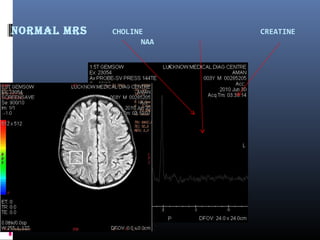

Normal mrS CHOLINE CREATINE

NAA

 Time of echo: 35 ms and 144ms.

 Resonance frequencies on the x-axis and amplitude (concentration) on the y-

axis.